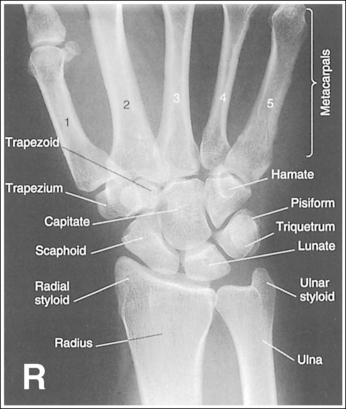

See Figure 4-29 and Box 4-11.

The wrist is positioned in a PA projection. The radial and ulnar styloids are at the extreme lateral and medial edges, respectively, of each bone. The radioulnar articulation is open, and superimposition of the metacarpal bases is limited.

• Rotation of the wrist and forearm is controlled by the position of the hand, elbow, and humerus. A PA projection is accomplished by abducting the humerus until it is positioned parallel with the IR and the elbow is in a lateral projection. The hand is then pronated, placing the wrist in a PA projection (Figure 4-31).

• Detecting wrist rotation and radial styloid position. When the hand and wrist are rotated externally into an externally rotated PA oblique projection, the carpal bones and metacarpal bases located on the medial aspect of the wrist are superimposed, whereas those located laterally are not. The lateral interconnecting carpal and metacarpal joint spaces are also demonstrated (see Image 31). Internal rotation of the hand and wrist causes the laterally located carpal bones and metacarpal bases to be superimposed and increases visibility of the pisiform and hamate hook (see Image 32).

• External and internal hand and wrist rotation also cause the radial styloid to rotate out of profile and closes the radioulnar articulation.

• Humerus and elbow positioning and ulnar styloid visualization. Humerus and elbow positioning determines the placement of the ulnar styloid. Abducting the humerus to position the elbow in a lateral projection with the humeral epicondyles aligned perpendicularly to the IR brings the ulnar styloid in profile and aligns the radius and ulna parallel with each other. The ulna and radius cross each other if the humerus is not abducted but is allowed to remain in a vertical position with the humeral epicondyles closer to parallel with the IR. This inaccurate positioning can be identified on a PA wrist projection by viewing the ulnar styloid, which is no longer demonstrated in profile (see Image 38).

The distal radius is demonstrated without foreshortening. The anterior and posterior articulating margins of the radius are nearly superimposed.

• The distal radial carpal articular surface is concave and slants approximately 11 degrees from posterior to anterior. Because the forearm is positioned parallel with the IR for a PA wrist projection, the slant of the distal radius causes the posterior radial margin to project slightly (0.25 inch or 0.6 cm) distal to the anterior radial margin, obscuring the radiocarpal joints.

The second through fifth CM joint spaces are open. The scaphoid is only slightly foreshortened, and the lunate is trapezoidal.

• When the wrist is placed in a neutral nonflexed position, these three alignments are achieved. To place the wrist in a neutral position, flex the patient's fingers, flexing the hand until the metacarpals are angled to approximately 10 to 15 degrees with the IR.

The long axes of the third metacarpal and the midforearm are aligned with the long axis of the collimated light field. The scaphoid and half of the lunate are positioned distal to the radius.

The carpal bones are at the center of the exposure field. The carpal bones, one fourth of the distal ulna and radius, and half of the proximal metacarpals are included within the collimated field.

• The wrist joint is located at a level just distal to the palpable ulnar styloid. To obtain an image of the carpal bones with the least amount of distortion, place a perpendicular central ray at this level and centered to the midwrist area. Open the longitudinal collimation to include half of the metacarpals. Transversely collimate to within 0.5 inch (1.25 cm) of the wrist skin line.

The wrist is a very complex joint, with numerous bony components and movement possibilities. In an attempt to simplify the effect that different upper extremity movements have on the bony components, the following summary is offered. The positions of the elbow and hand affect forearm and wrist rotation and can be identified by the positions of the ulnar and radial styloid, respectively. When the elbow is in a lateral projection (humeral epicondyles aligned perpendicularly to IR), the ulnar styloid is in profile. When the hand is in a PA projection, the radial styloid is in profile.